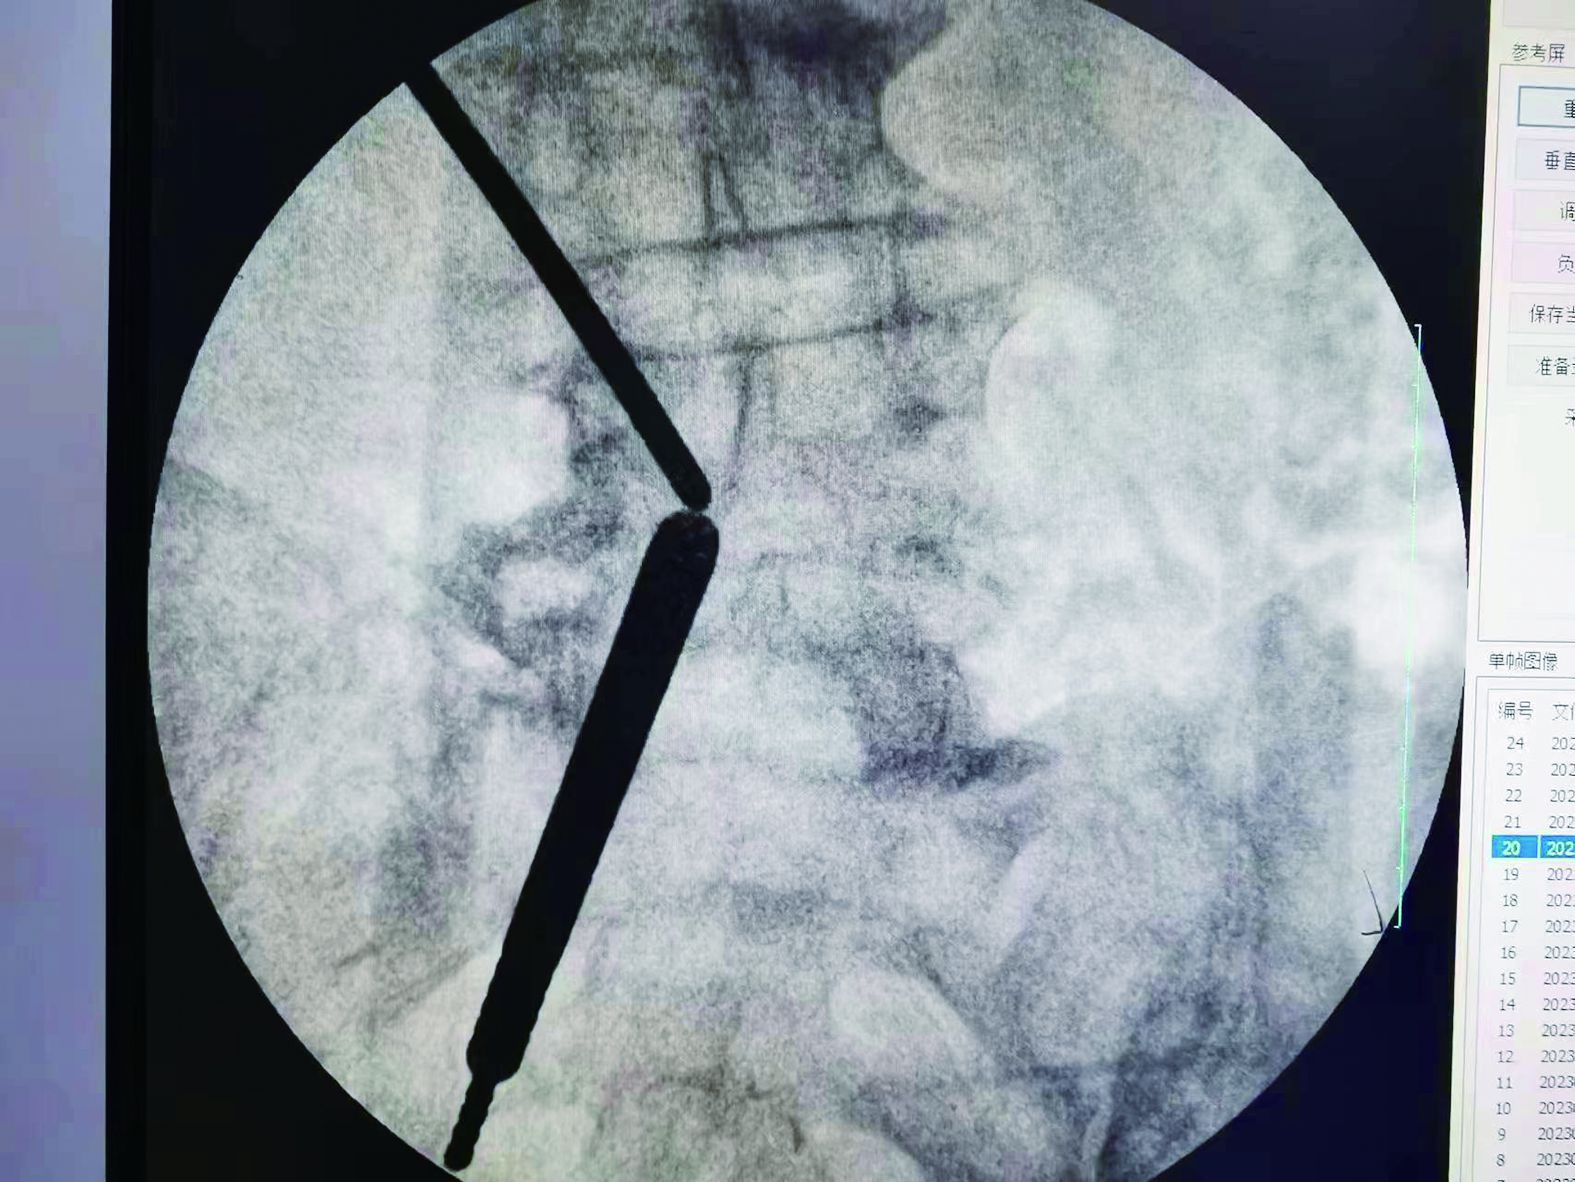

▲建立手術(shù)通道

▲術(shù)中定位

據(jù)了解,患者楊爺爺今年70歲,因腰部及左下肢疼痛10天入院,入院時查體,左側(cè)大小腿壓痛,直腿抬高試驗陽性,感覺減退,肌力無減退。CT及MRI提示:腰3-4椎間盤突出、椎管狹窄,入院后經(jīng)正規(guī)保守治療2周,腰部及左下肢疼痛無緩解。為盡快緩解患者癥狀,達到早日康復(fù)目標(biāo),李建偉和骨科團隊進行了周密的術(shù)前討論和規(guī)劃,決定舍棄傳統(tǒng)手術(shù)方案,為患者制定了“UBE(單側(cè)雙通道脊柱內(nèi)鏡技術(shù))下椎管減壓、椎間盤髓核摘除”微創(chuàng)治療方案。

經(jīng)過精密的術(shù)前準(zhǔn)備,術(shù)中使用UBE專用器械和等離子射頻手術(shù)系統(tǒng),視野清晰,操作靈活,椎板減壓,在保護神經(jīng)根和硬膜囊的前提下輕松摘除脫出的椎間盤髓核,與傳統(tǒng)手術(shù)相比,該手術(shù)方式兼具微創(chuàng)、安全、有效、并發(fā)癥少等顯著優(yōu)勢,病人背部只有兩個2cm的小切口。患者術(shù)后腰腿疼痛癥狀消失,術(shù)后第二天即可下床行走,手術(shù)效果顯著,得到了患者及家屬的高度認(rèn)可。